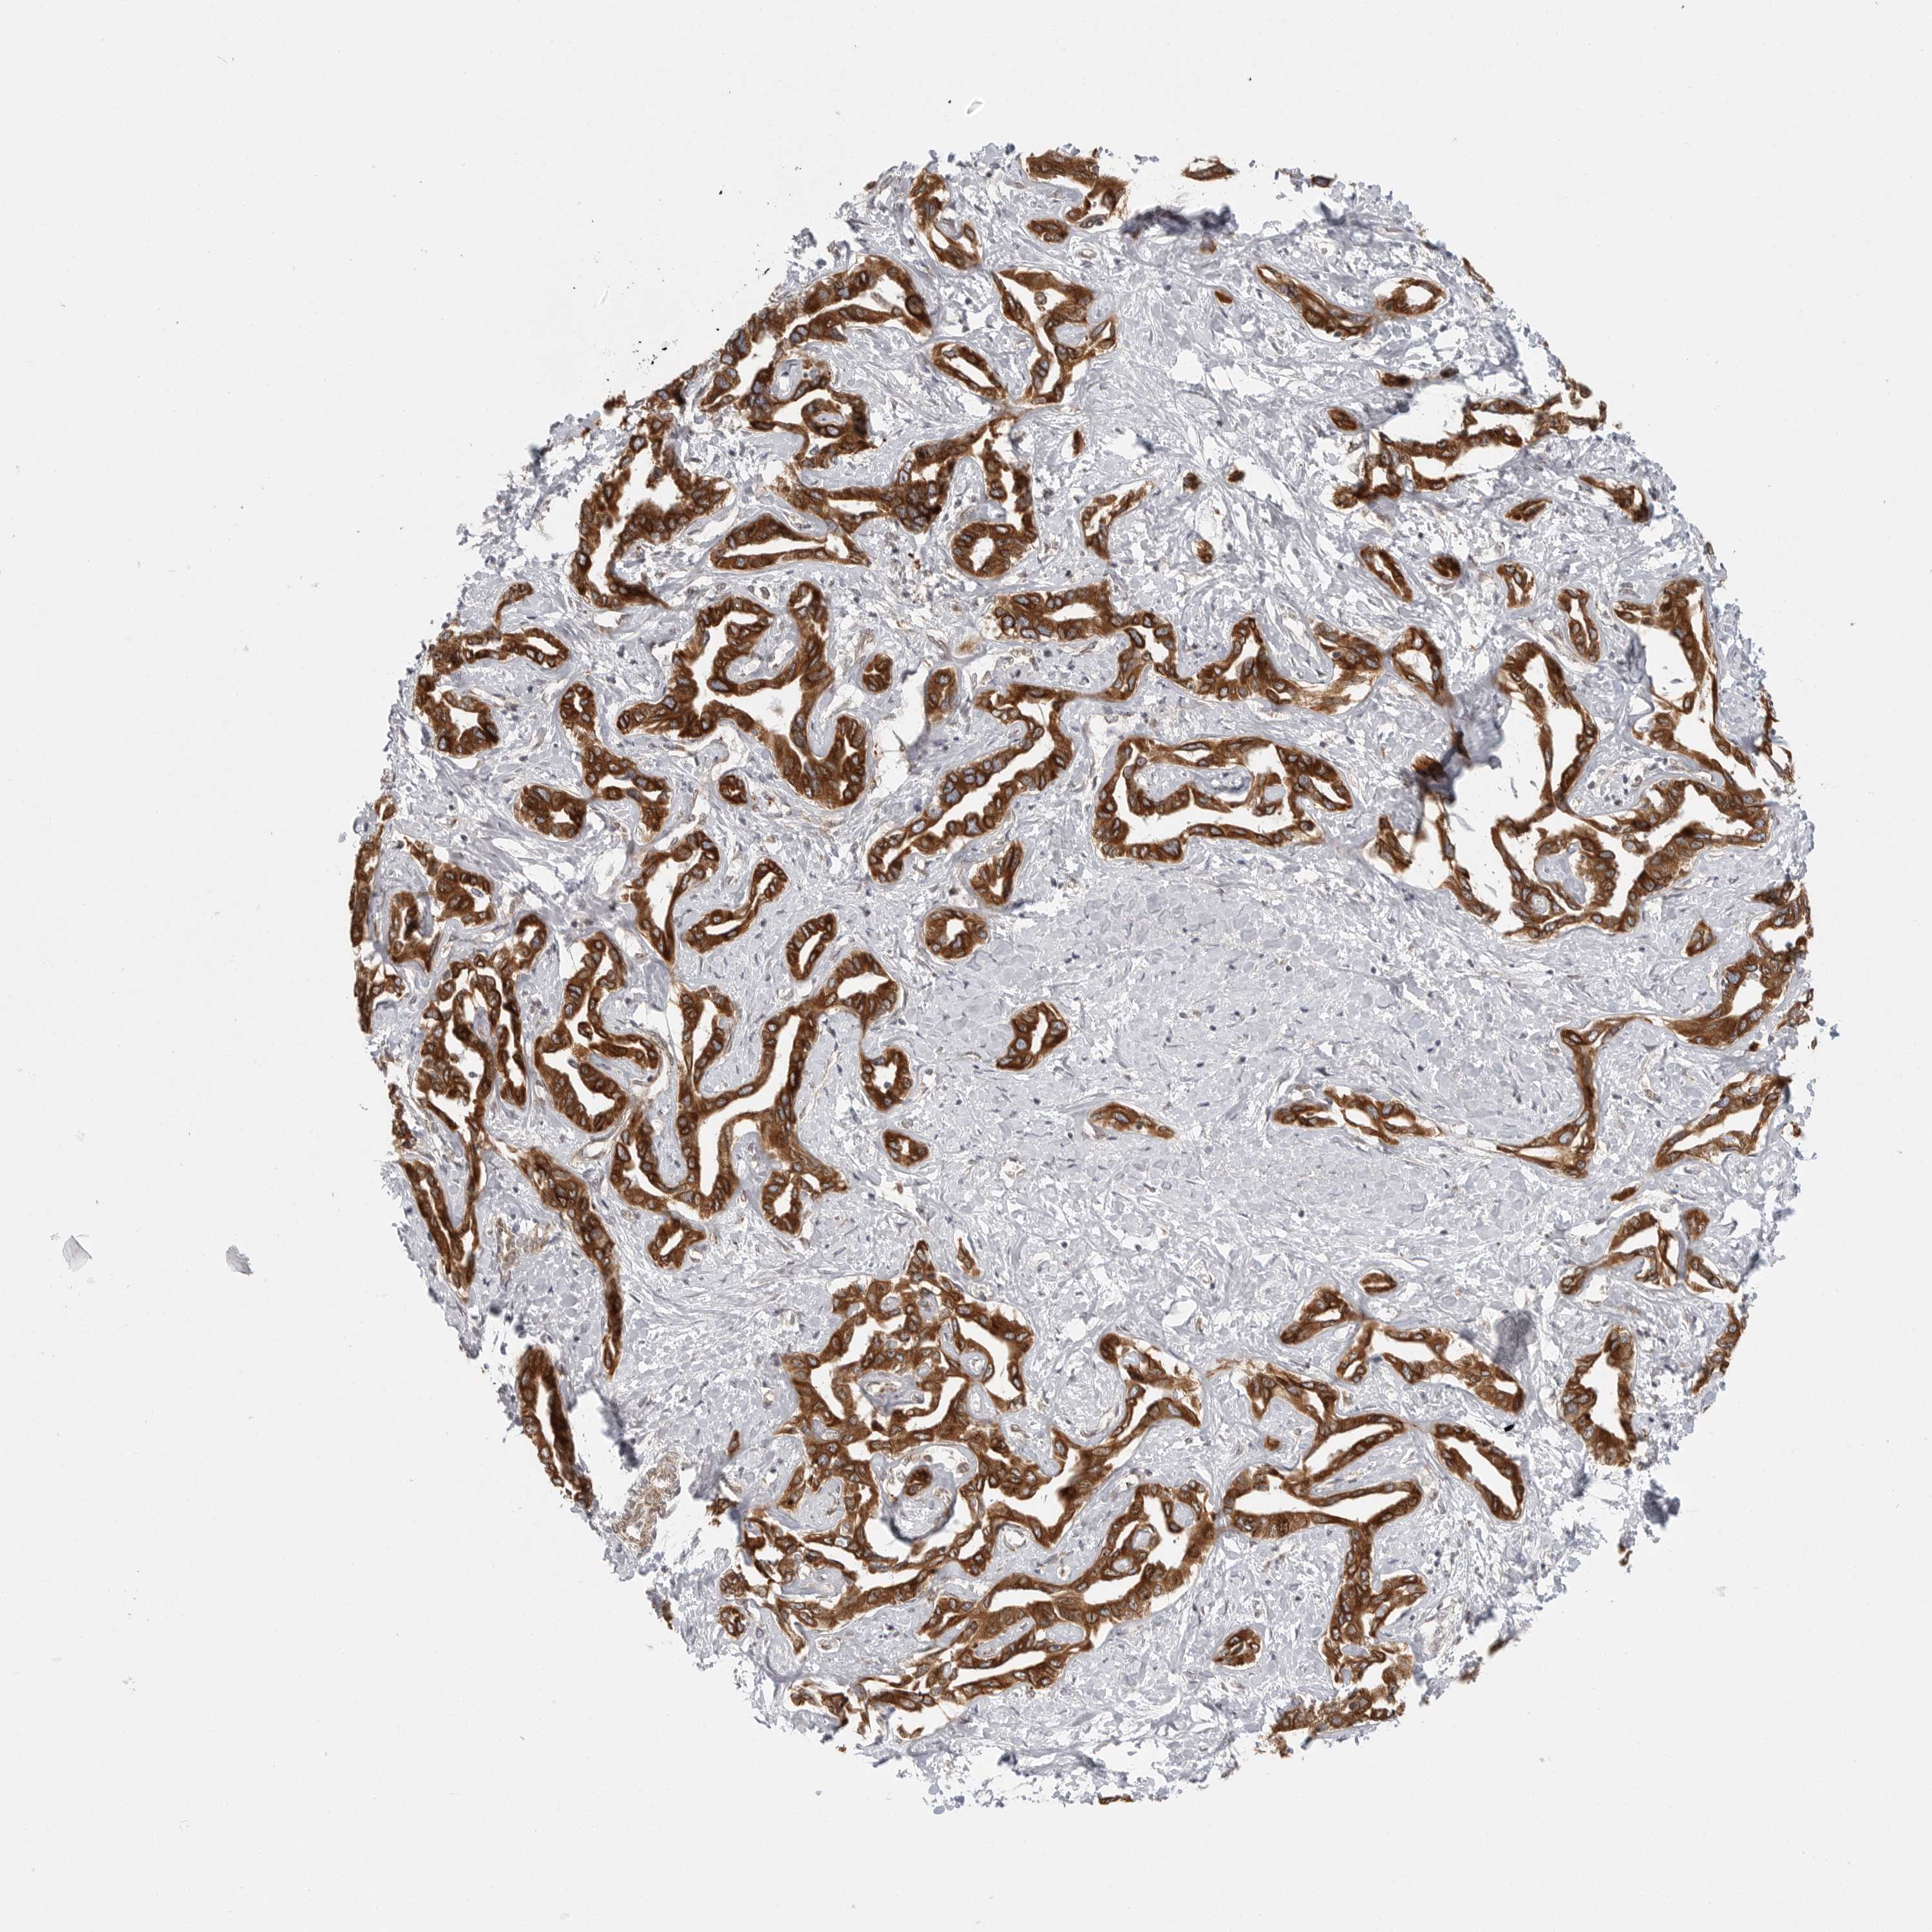

LIVER CANCER - Protein expressioni

A mouse-over function shows sample information and annotation data. Click on an image to view it in a full screen mode. Samples can be filtered based on level of antibody staining by selecting one or several of the following categories: high, medium, low and not detected. The assay and annotation is described here.

Note that samples used for immunohistochemistry by the Human Protein Atlas do not correspond to samples in the TCGA dataset.

Antibody stainingi

Antibody staining in the annotated cell types in the current human tissue is reported as not detected, low, medium, or high, based on conventional immunohistochemistry profiling in selected tissues. This score is based on the combination of the staining intensity and fraction of stained cells.

Each image is clickable and will lead to virtual microscopy that enables deeper exploration of all samples and also displays staining intensity scores, fraction scores and subcellular localization as well as patient and tissue information for each sample.

Antibody HPA027262

Antibody HPA078737

Cholangiocarcinoma

Carcinoma, Hepatocellular, NOS